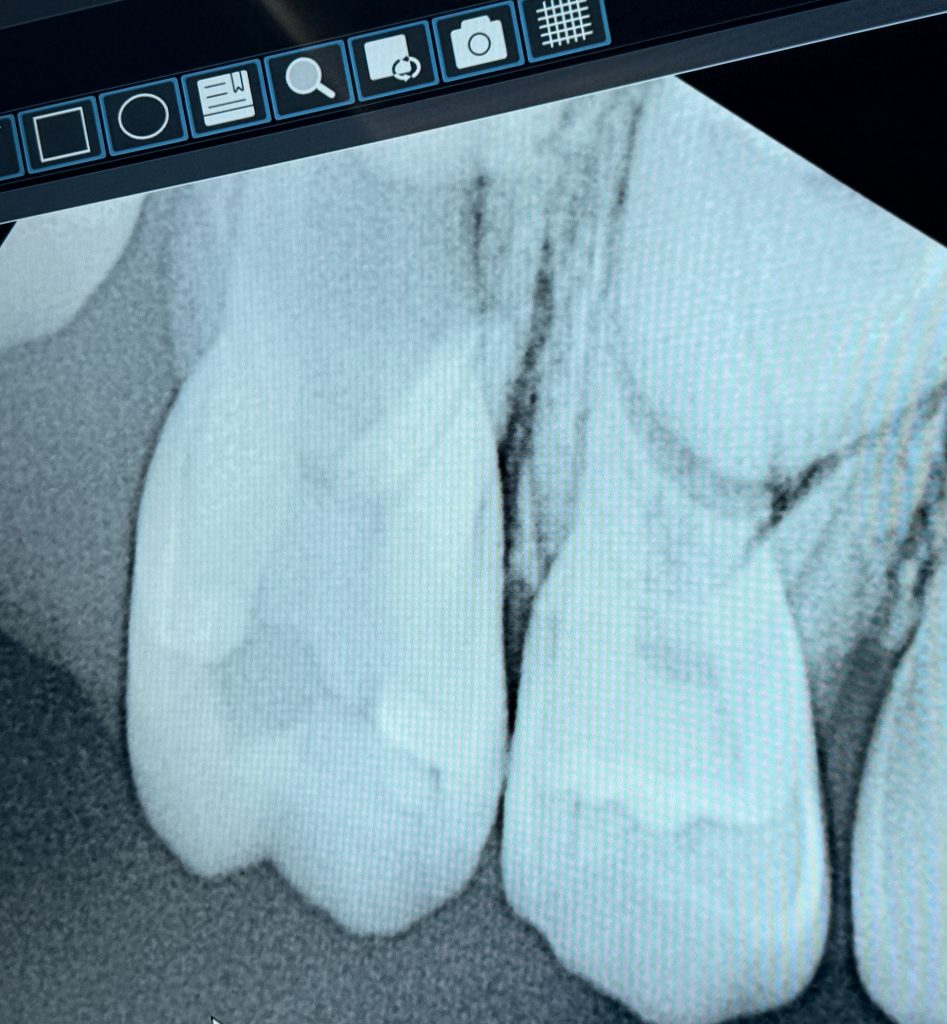

A child patient presented with spontaneous pain and deep caries on a mandibular primary molar (Fig 1). Radiograph revealed pulpal involvement with resorbable root structure yet sufficient length for obturation.

- Fig 1: Pre-operative radiograph showing deep caries in primary molar.